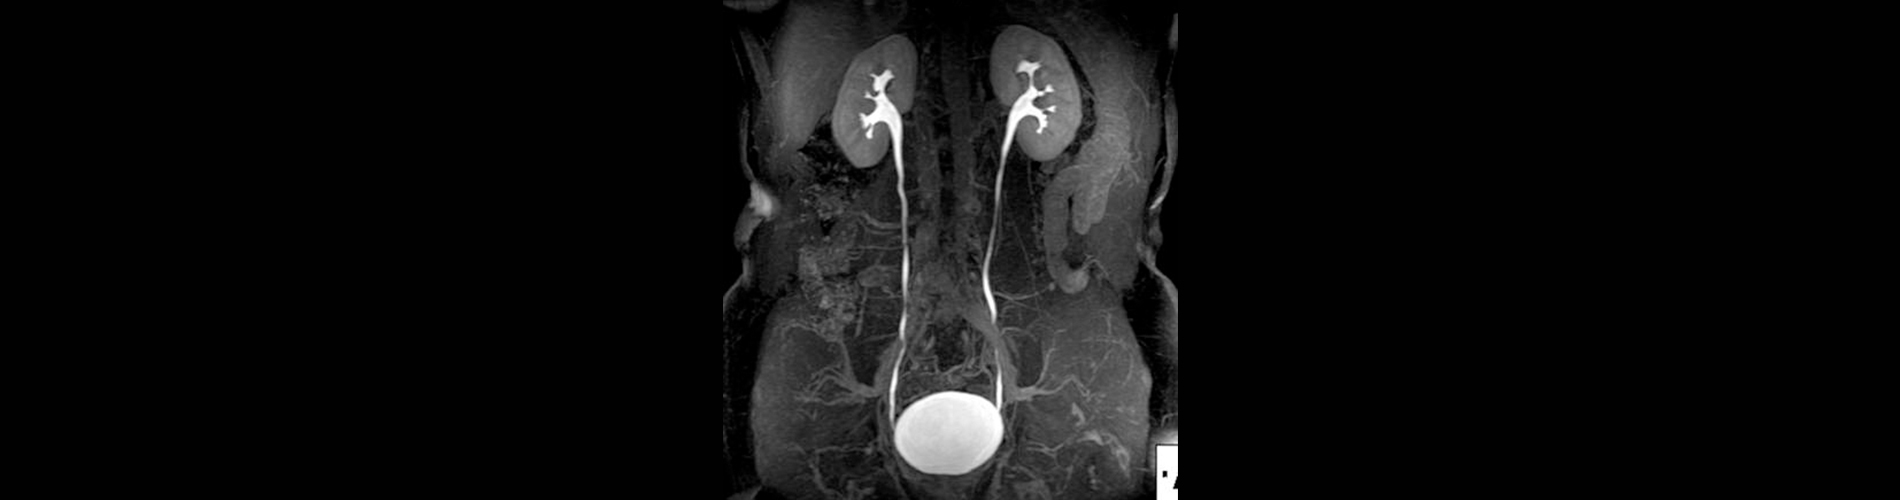

Ürografi MR Nedir?

• Hedef Bölge: Böbrekler, üreterler (idrar yolları), mesane ve çevresindeki yapılar.

• Yüksek Çözünürlük: İdrar yollarının detaylı anatomik ve fonksiyonel görüntülerini sağlar.

Ürografi MR’ın Kullanım Alanları

• Böbrek ve Üreter Taşları: Taşların boyutu, konumu ve tıkanıklığa neden olup olmadığını belirleme.

• Hidronefroz: Böbreklerde sıvı birikimine neden olan tıkanıklıkların tespiti.